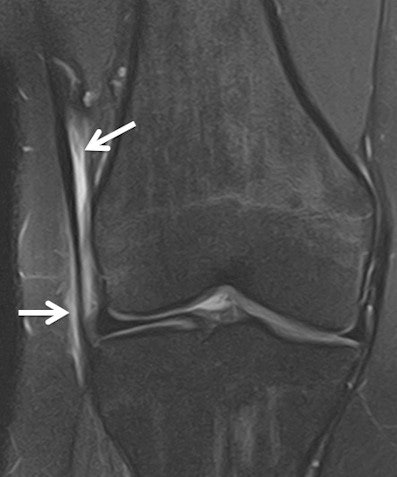

However, in the run to the games they have seen several typical sports injuries, including a fatigue stress fracture in the heel of a long distance runner and a case of iliotibial band syndrome in the knee of a hockey player (see images).